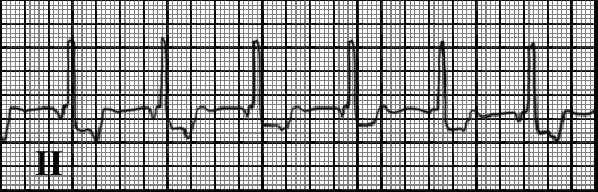

You are incorrect - our patient's rhythm strip shows atrial fibrillation.

The characteristic features demonstrated here include regular P waves associated with each QRS, with the P waves negative in lead II due to retrograde atrial conduction; a constant PR interval; and a rate ranging from 60 to 100 beats per minute.

In some cases, the P wave follows the QRS, as the atrium is depolarized after the ventricle. In other cases, no P wave is seen, as depolarization is concurrent.

Accelerated junctional rhythm may be benign and in some cases it is associated with right coronary artery disease.